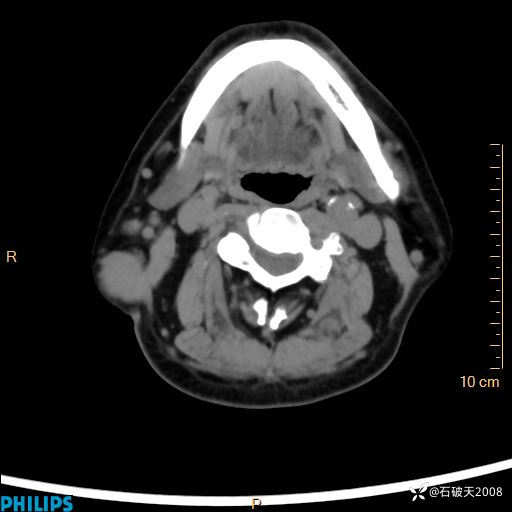

静脉期